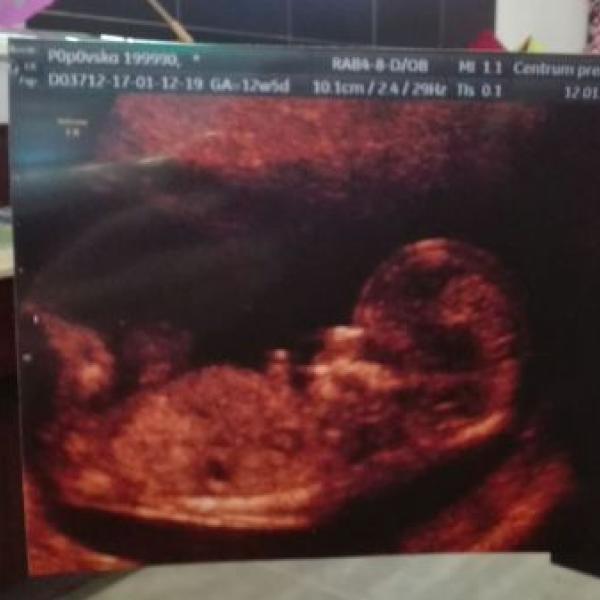

Ahoj holky, dneska jsem absolvovala NT+ vyšetření. Přítel poprvé viděl svoje miminko a byl hrozně unešený. Projasnění má prďolka 1.3, takže úplně super. Odpovídá na den přesně, takže dle MS i ultrazvuku bude termín 22.7.2017 (přítel je 17.7. tak se třeba poštěstí). Jen mě mrzí, že nás paní doktorka trochu ošidila... Tady vidíte ruky, nohy, srdce, fotku vám natisknu a výsledky budem volat - nashle. Myslím, že se vším všudy jsme byli za 5minut venku... Ale i tak jsme oba nadšení!